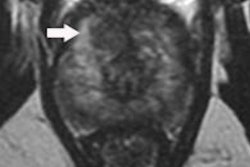

Multiparametric MRI of the prostate can be a complex examination. All images courtesy of Dr. Vibeke Logager.

Multiparametric MRI of the prostate can be a complex examination. All images courtesy of Dr. Vibeke Logager.Radiologists need to benchmark themselves against good quality standards, and he urges ECR 2019 delegates to get involved in the process because they have a vested interest in doing this. He hopes today's session will stimulate mature discussion to a wide audience and boost acceptance of quality checking toward establishing an accredited program. The most important contribution toward accreditation is face-to-face discussions in a multidisciplinary team. This is highly valued because it brings the benefits of timely feedback, which is a vital component of improved care, he added.